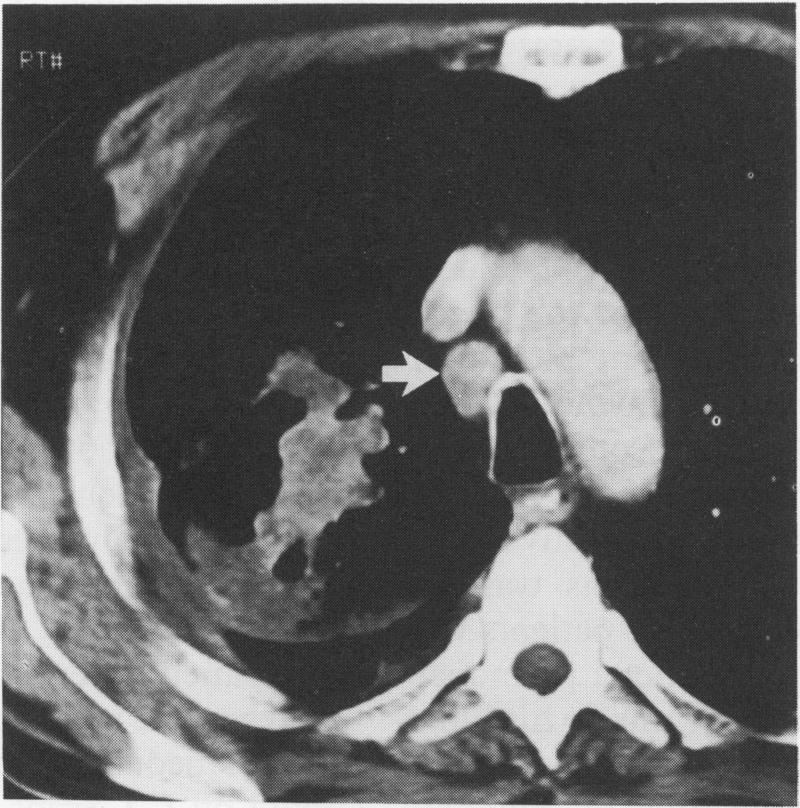

支气管癌的术前分期:计算机断层扫描能否可靠地识别Ⅲ期肿瘤?

Preoperative staging of carcinoma of the bronchus: can computed tomographic scanning reliably identify stage III tumours?

The aim of preoperative computed tomographic (CT) assessment of patients with carcinoma of the bronchus is to stage the tumour accurately, and forewarn the surgeon of any possible local extrapulmonary extension of tumour in patients considered to have potentially resectable disease. The ability of CT scanning to differentiate between conventionally resectable lung cancer (TNM stages I and II), locally advanced but resectable lung cancer (TNM stage IIIa), and locally advanced but unresectable lung cancer (TNM stage IIIb) was determined in a group of patients accepted for surgery.

METHODS

Computed tomographic scans of 110 patients who underwent thoracotomy for intended resection of carcinoma of the bronchus, including 52 cases with stage III and 58 cases with stage I or II disease, were reviewed and the CT features and radiological interpretations correlated with the surgical and pathological findings.

RESULTS

Thirteen CT scans were judged not to have been of diagnostic quality: of the remaining 97 cases 45 had stage III lung cancer, of whom 30 had successful resections, and 52 had stage I or stage II tumours. There was no difference in the frequencies of CT observations--including contiguity of tumour and mediastinum or chest wall, apparent mediastinal or chest wall invasion, proximity of tumour to the carina, mediastinal nodal enlargement, pulmonary collapse or consolidation and pleural effusion--in patients with stage I/II disease and patients with stage III disease. Similar results were found when the same observations were compared in all patients with resected disease and those with unresectable tumour. Sensitivity and specificity of CT was 27% and 96% respectively for tumour unresectability, 50% and 89% for mediastinal invasion, 14% and 99% for chest wall invasion, and 61% and 76% for mediastinal nodal metastases. Only 19 of 45 stage III tumours were correctly identified as being stage III and resectable or unresectable.

CONCLUSIONS

In patients being considered for thoracotomy for resection of lung cancer, CT scanning used as the sole method of staging is of limited value for differentiating between stage I/II and stage III tumours. Patients should not be denied the opportunity for curative surgery on the basis of equivocal CT signs.

对支气管癌患者进行术前计算机断层扫描(CT)评估的目的是准确对肿瘤进行分期,并在认为可能可切除的患者中,预先警告外科医生肿瘤任何可能的肺外局部扩展情况。在一组接受手术的患者中,确定了CT扫描区分传统可切除肺癌(TNM分期I期和II期)、局部晚期但可切除肺癌(TNM分期IIIA期)以及局部晚期但不可切除肺癌(TNM分期IIIB期)的能力。

方法

回顾了110例因计划切除支气管癌而接受开胸手术患者的CT扫描结果,其中包括52例III期患者和58例I期或II期患者,并将CT特征及影像学解释与手术和病理结果进行关联。

结果

13份CT扫描被判定诊断质量不佳:在其余97例病例中,45例为III期肺癌,其中30例成功切除,52例为I期或II期肿瘤。I/II期疾病患者和III期疾病患者在CT观察结果(包括肿瘤与纵隔或胸壁的连续性、明显的纵隔或胸壁侵犯、肿瘤与隆突的距离、纵隔淋巴结肿大、肺不张或实变以及胸腔积液)的频率上没有差异。在所有可切除疾病患者和不可切除肿瘤患者中比较相同观察结果时,也发现了类似结果。对于肿瘤不可切除,CT的敏感性和特异性分别为27%和96%;对于纵隔侵犯,分别为50%和89%;对于胸壁侵犯,分别为14%和99%;对于纵隔淋巴结转移,则分别为61%和76%。45例III期肿瘤中只有19例被正确判定为III期且可切除或不可切除。

结论

在考虑行开胸手术切除的患者中,仅将CT扫描用作分期方法在区分I/II期和III期肿瘤方面价值有限。不应基于不明确的CT征象而剥夺患者进行根治性手术的机会。